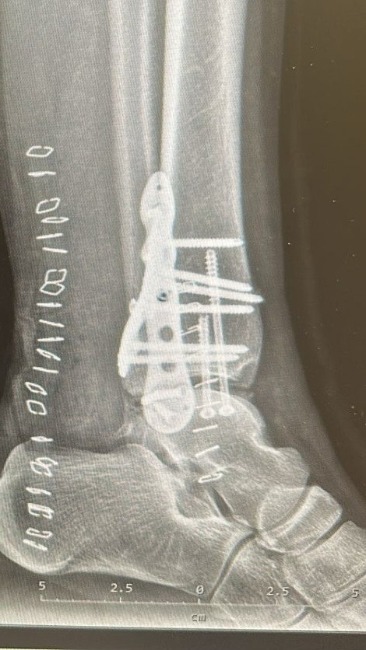

W szpitalu diagnoza brzmiała: poważne, trójkostkowe złamanie w stawie skokowym. Jeszcze tego samego dnia przeszła skomplikowaną operację. Dziś jej noga jest scalona licznymi śrubami i blaszkami.